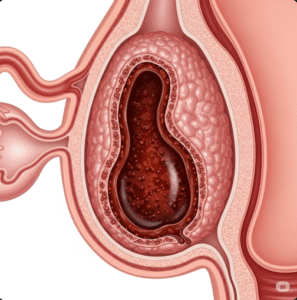

Unicameral Bone Cyst (UBC) is a benign, fluid-filled cavity that forms within a bone, most commonly in children and adolescents. These cysts typically develop in long bones such as the femur or humerus and are often discovered incidentally during X-rays for minor injuries. While they are non-cancerous and often asymptomatic, they can weaken the bone and increase the risk of fractures. Treatment depends on the size, symptoms, and risk of bone damage.

Unicameral Bone Cyst (UBC), also known as a Simple Bone Cyst, is a solitary, non-cancerous cavity within a bone that is filled with clear fluid. It usually occurs in the metaphysis—the growing end—of long bones like the upper arm (humerus) or thigh bone (femur). UBCs are most commonly diagnosed in children between the ages of 5 and 15 and tend to be discovered when a child suffers a fracture through the weakened bone. These cysts typically resolve with skeletal maturity, but some may require surgical intervention.